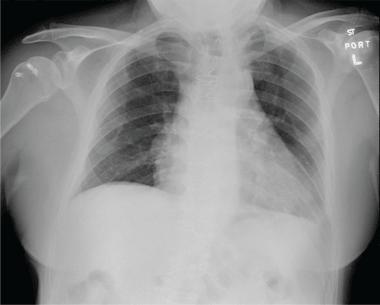

The ropivacaine infusion was stopped

๐Ÿ‘‰ the supraclavicular catheter was removed under anesthesia

๐Ÿ‘‰ over the course of 8 to 12 hours his shortness of breath resolved

๐Ÿ‘‰ lung examination normalized

Repeat chest radiography 24 hours after ๐Ÿ‘‡